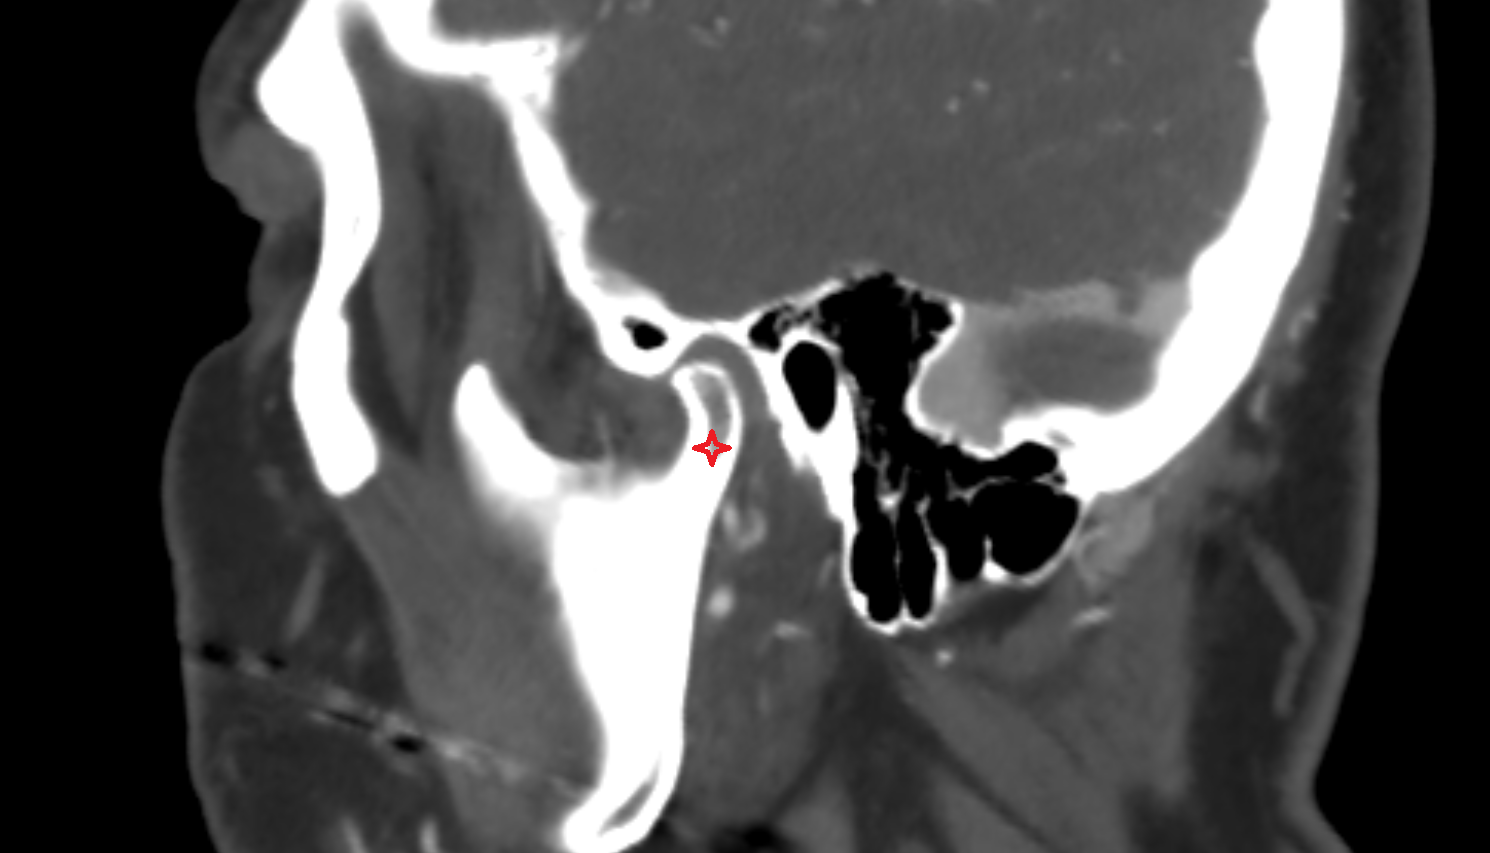

- Temporomandibular joint

- Mandibular condyle

- Mandibular fossa

- Articular disc of temporomandibular joint

- Articular eminence